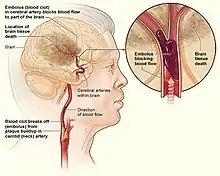

A neonatal arterial ischemic stroke occurs when the blood vessels of the brain are partly or completely blocked. This situation normally affects the middle cerebral arterial region.[9] This subgroup of perinatal stroke affects between 5 and 43 babies in 100,000 live births.[10] A recent multinational cohort study showed that stroke or succeeding deficits caused the death of 65% of the patients who were suffering from neonatal arterial ischemic stroke.[11] Risk factors such as maternal fever,[12] gestational diabetes and having a record of miscarriage experiences will increase the occurrence of neonatal arterial ischemic stroke.[13] However, the definitive etiology of neonatal arterial ischemic stroke remains uncertain to date.[1]

Birth trauma and mechanical trauma to the fetal head and neck can cause stroke by damaging arteries: Some children may have arteries that are damaged by trauma or inflammation leaving a rough or jagged inner lining where blood clots can get stuck. These clots can build up enough so that eventually the artery is clogged and no blood can flow through.[23] In addition to vascular damage, trauma to the fetal head from excessive uterine activity, manipulation, pressure, and forceps or vacuum application via direct occlusion or vasospasm can cause perinatal ischemic stroke.[24]